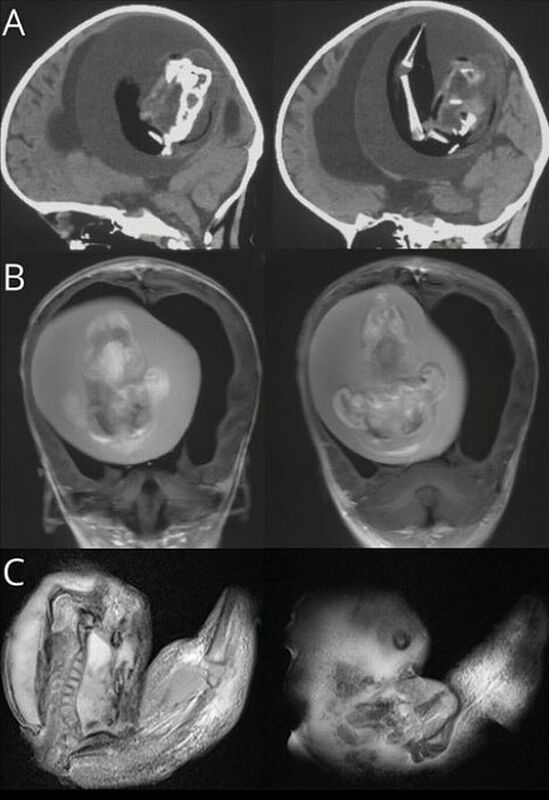

Ảnh chụp CT bào thai sống trong não bé gái.

Khi thấy bé gái một tuổi đầu phình to bất thường, có vấn đề về kỹ năng vận động, khi được đưa đến bệnh viện chụp CT cho thấy một bào thai sống đang đè lên não của bé.

Bác sĩ Bệnh viện Hoa Sơn, Đại học Phúc Đán, nhận định ban đầu đây là một cặp song sinh nhưng vì lý do nào đó một thai nhi đã phát triển và bao bọc người chị em của mình. Bào thai trong đầu của bé gái tiếp tục phát triển nhiều tháng như khi còn trong bụng mẹ, đã có chi trên, xương và móng tay.

Các bác sĩ đã phẫu thuật để loại bỏ bào thai trong đầu của bé. Tuy nhiên, do tổn thương lâu dài, họ chưa chắc chắn liệu em có thể sống sót hay không.